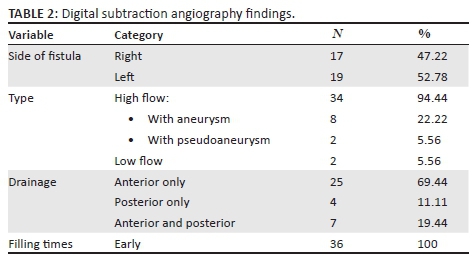

A total of four patients who did not undergo intervention or did not comply with follow-up were excluded from the subsequent analysis (n = 4). The reasons for exclusion are documented in Table 1. Although most patients presented with a single fistula, a few exceptions (n = 3) were noted with two simultaneous fistulas. For ease of statistical analysis, each fistula was analysed independently. A total of 36 fistulas in 34 patients were considered for analysis. DSA findings are presented in Table 2. The fistulas were classified according to their flow dynamic, cause and the presence of aneurysm or pseudoaneurysm. High-flow fistulas were present in all but two patients (n = 34, 94.44%). There was early filling of the affected CS in all patients. The fistulas did not favour a particular side and had predominantly anterior drainage only (n = 25, 69.44%). Aneurysms were identified in eight patients (22.22%) and psuedoaneurysms in two cases (5.56%). All patients passed the trial balloon occlusion test, suggesting adequate collateral blood flow.

Fistula occlusion was attained via embolisation or trapping in all cases that were compliant with management and in whom intervention was attempted (n = 36, 100%). Sacrifice of the affected ICA was required in 10 patients (27.78%). Reasons for sacrifice are demonstrated in Figure 6. No documented post-procedural complications were noted.

One of the patients presented post-trauma, with bilateral high-flow fistulas. Multiple balloons were deployed bilaterally, which resulted in reduced filling but persistence of the fistula. A repeat angiogram was then performed at a later date. The right fistula, which was smaller, was treated successfully using a covered stent (Jo stent). The left fistula, however, was larger and required sacrifice of the left ICA to occlude the fistula. In Table 3, the relationship between outcome and demographic data, the side of fistula and presence of an aneurysm, respectively, is presented. Sacrifice of the ICA was slightly higher in those who had an intracavernous ICA aneurysm compared to those who did not (37.5% vs. 25%); however, this finding was not statistically significant (p = 0.658). A higher rate of ICA sacrifice was also observed in fistulas on the right side (35.3% vs. 21.1%); this result was also not statistically significant (p = 0.463).

At DSA, the supplying arterial structures in low flow fistulas, the breech in the vessel wall in high-flow fistulas and venous drainage pattern can be easily assessed.4 Early contrast enhancement of the affected CS usually indicates the presence of a fistula (see Figure 10). Anterior venous drainage patterns are the commonest drainage pathway1 which is further supported by our study and accounts for the predominance of orbital/ocular signs. Specific assessment for cortical venous drainage at angiography is advised as urgent treatment is indicated, if present, because of its association with potentially life-threatening sub-arachnoid/intracerebral haemorrhage.9

Assessing the arterial supply allows classification of the CCF by means of the Barrow's classification. This classification was found to be confusing and did not add further value in terms of further management. In our experience, classifying the fistula according to its flow dynamic and documenting the presence of an intracavernous aneurysm or pseudoaneurysm was found to be more practical (see Figure 11).